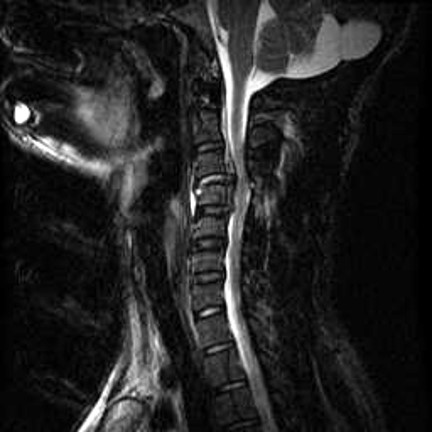

There were tubes in my arms, up my nose, and down my throat, and a neck brace stabilizing my freshly fused cervical spine. I was numb from the neck down, everything I could feel was on fire, and the future was as unclear as the whereabouts of my limbs. Never in my wildest dreams could I have imagined that I would wake up 17 years later to the giggles, coos, and grunts of an almost five-month-old little girl, the latest (and, by far, greatest) in a string of miracles that have made up this wild second act of my story.

I found a quote recently by English novelist and poet, George Meredith, that says, “There is nothing the body suffers the soul may not profit by.” With all my body has endured – the broken neck, two fractured thoracic vertebrae, one snapped femur, a burst appendix, four different stage IV pressure sores, close to a dozen kidney stone surgeries, countless urinary tract infections, and a near-death experience from sepsis – it was probably inevitable that I started seeing things through a far more spiritual lens.